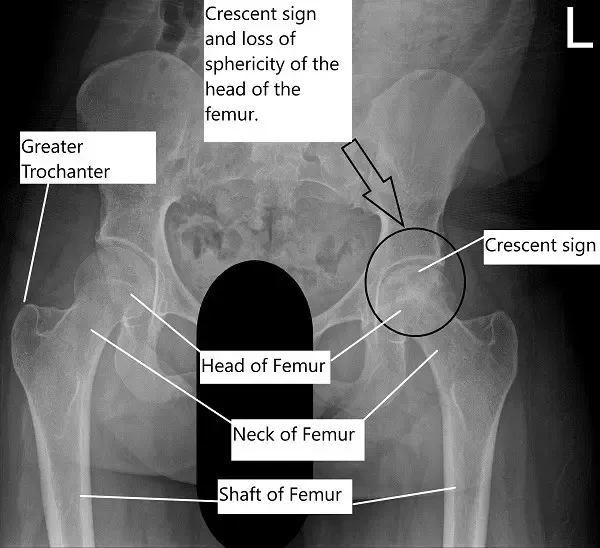

On radiological investigations, the X-ray of the left hip revealed avascular necrosis of the head of the femur with subchondral collapse visible in the form of a crescent sign. The X-ray of the right hip revealed a normal radiograph.